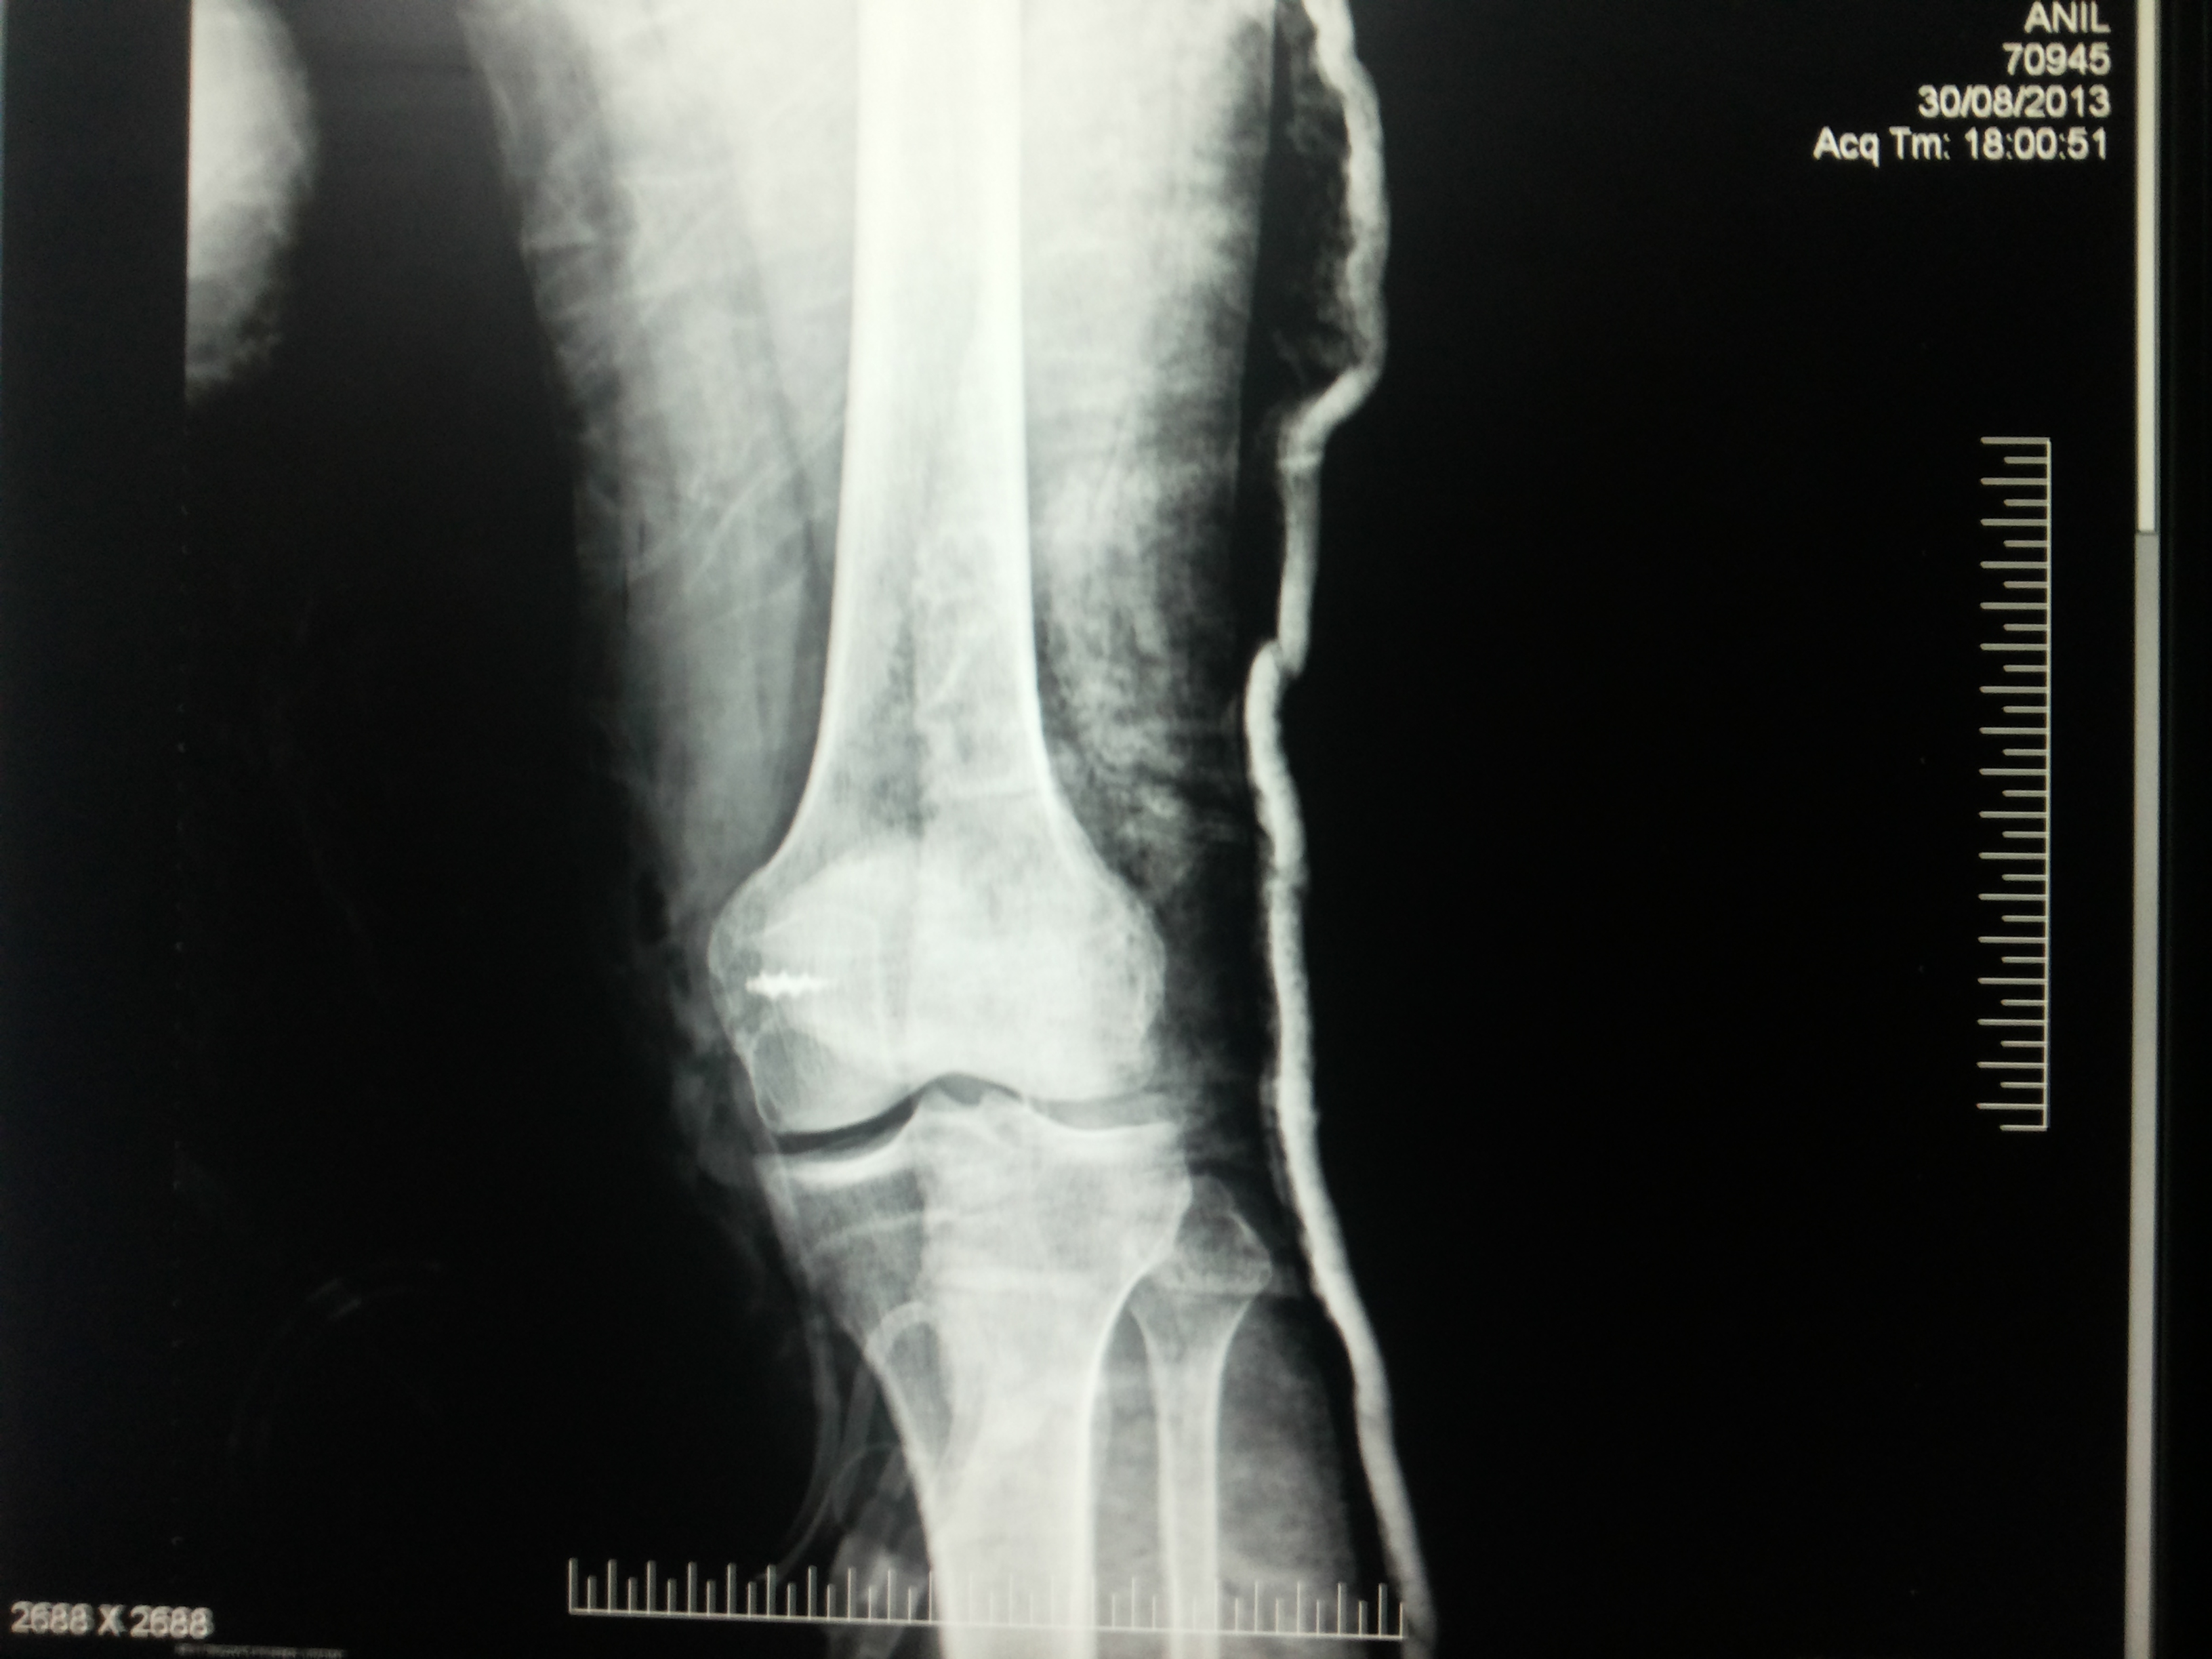

What is multi-ligament knee Injury?

Multiple ligament knee injuries happen when more than one of the knee’s ligaments is torn. They are less common than single ligament injuries.

What causes Multi-Ligament Knee Injury?

Multiple ligament knee injuries can occur during sports activities or through high-energy trauma, such as a fall from height or a car accident.

How Multi-ligament knee Injury diagnosed?

The most important way to initially diagnose these injuries is to review a thorough history with the patient to recall that their knee felt that it dislocated and slipped back in. It’s important to determine if this was solely their kneecap joint where there was a patellar (kneecap) dislocation or if it was the complete knee joint itself slipping out of place.

These injuries are very severe and potentially limb and life threatening. Thus, assessing for this and insuring that the patient’s knee function is intact, including both the status of the pulses to ensure that the artery is not injured as well as their sensation to ensure that there are no nerve injuries present is important.

How multi–Ligament Knee Injury Treated?

Nearly all cases of multiple ligament knee injury require surgery. The goal of surgery is to:

Restore knee stability

Regain full range of motion

Allow a return to athletic activities in the future

Before surgery, patients are prescribed physical therapy to work on regaining full motion and to decrease knee swelling. All patients wear a brace to protect the knee before surgery.